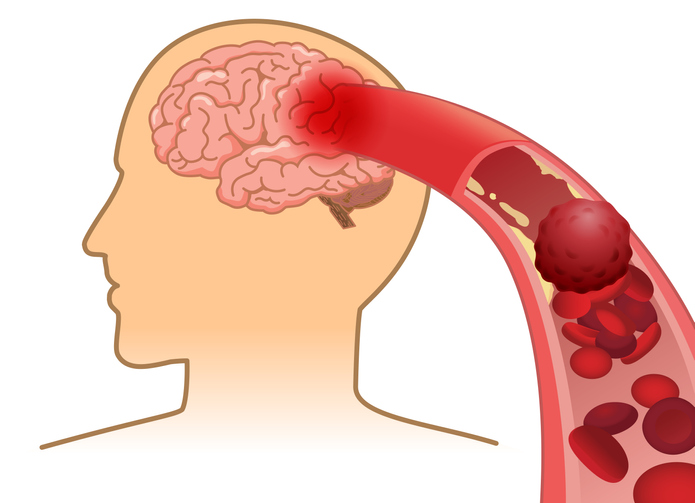

한국 사망원인 Top 5안에 들어갈 정도로 사망률이 높은 질환이라고 합니다. 뇌졸증은 뇌혈관이 터져서 손상이 나타나는 ‘출혈성 뇌졸증(뇌출혈)과 뇌혈관이 막혀서 나타나는 허혈성 뇌졸증(뇌경색)등으로 나뉠 수 있어요.

그 중에서 뇌출혈은 뇌 안에 있는 혈관인 뇌동맥에서 혈관 벽이 부풀어 올라 찢어지면서 혈액이 뇌 밖이나 안으로 흘러나와서 발생해요. 뇌동맥류가 파열되면 뇌와 척수 사이의 거미줄과 같이 생긴 공간에 혈액이 스며들게 되며 이런식으로 출혈이 일어나게 되면 30~절반이 사망에 이르게 돼요.

뇌출혈과 유사한 질환에 뇌경색이 있어요. 뇌경색과 뇌출혈은 한꺼번에 뇌혈관장애(뇌졸중)라고 불려요. 뇌경색이란 뇌의 혈관이 막히는 것으로 뇌세포에 혈액이 전파되지 않게 되는 질환이라고 합니다. 뇌혈관이 막히는 원인은 혈관 내부의 협착이라고 합니다. 아니면 혈전이라고 하는 핏덩어리가 혈관을 막을 수도 있어요.